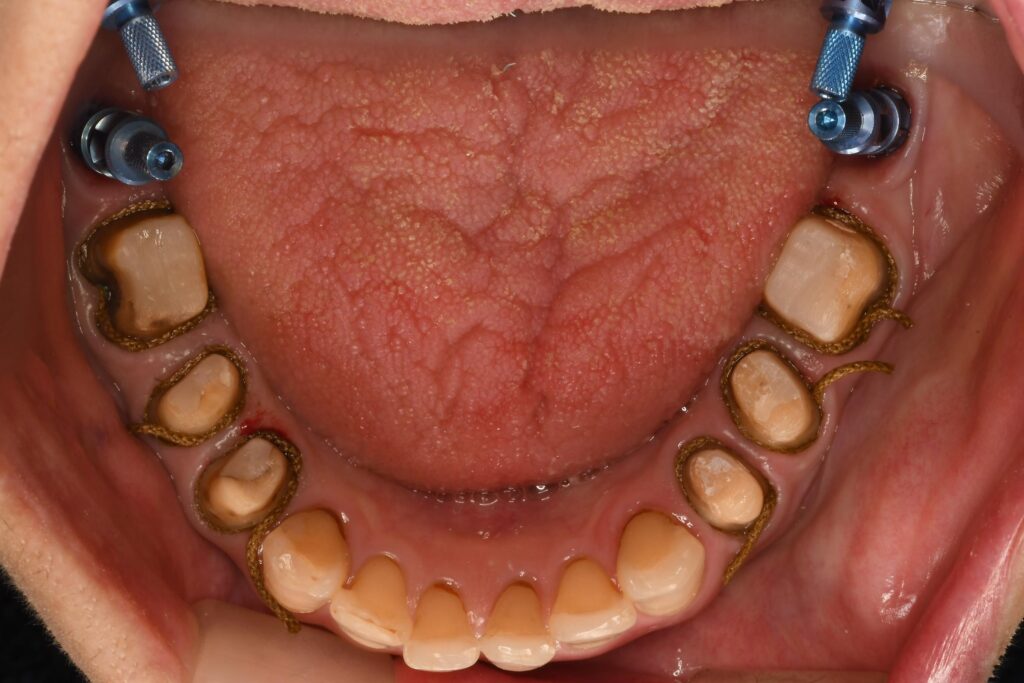

本日はインプラントを含めた「8本同時の型取り」を行いました

「歯科治療は何度も通うもの」そう思われがちですが、当院ではできる限り通院回数を少なくする治療を心がけています。